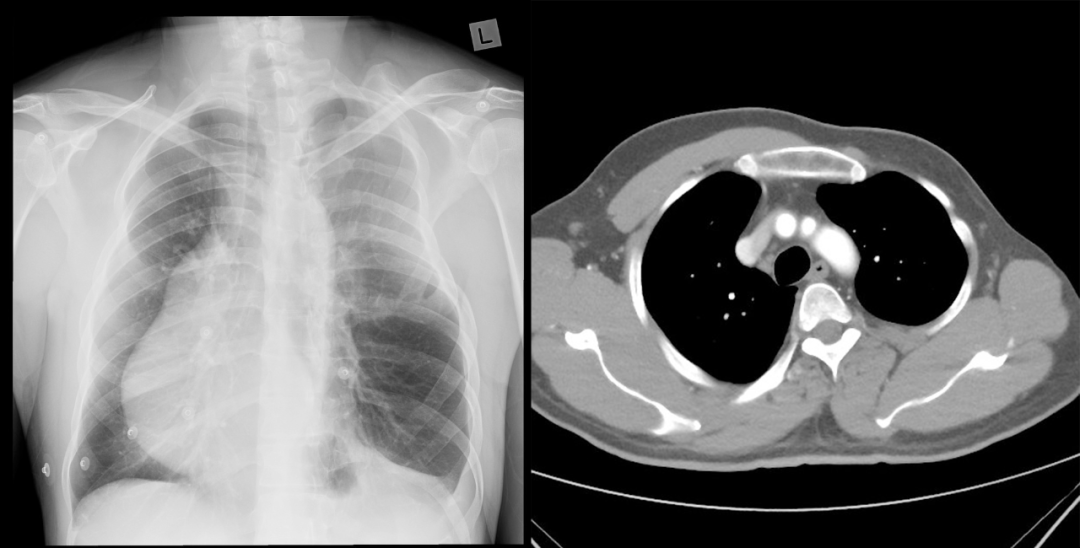

病例 3:左侧胸廓缩小,左侧胸大肌和胸小肌缺失,合并右位心

病例 4:胸部 X 线显示双侧乳头标记物高低不一致,右高左低,右肺野透亮度减低;右侧胸大肌及胸小肌缺失